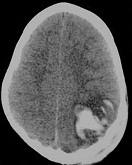

- 单项选择题男,3岁, 头颅被球击中,请结合CT图像, 选择最可能的诊断是 ( )

A、高血压性脑出血

B、脑结核

C、脑挫裂伤血肿形成

D、动脉瘤破裂出血

E、血管畸形